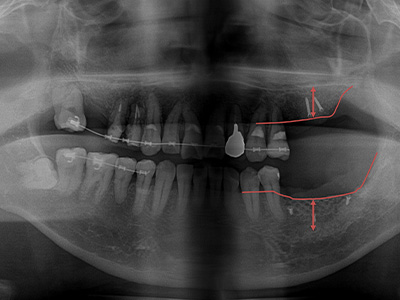

インプラント治療を検討される方の多くは、歯周病が原因で歯を失っており骨を増やす処置が必要になることも少なくありません。近年では、さまざまな骨造成技術の進歩により、これまで困難とされていた症例でも治療が可能になってきました。ただし、これらの処置には高度な技術が求められ、対応できる歯科医師が限られているのが実情です。

GBR

顎の骨の不足を補うために行う治療法です。骨を増やしたい部分に骨補填材を入れ、人工膜を被せて骨の再生を促します。歯ぐきを被せて閉じ、約4〜6ヶ月で骨が再生された後、次の治療に進みます。

ソケットリフト

(クレスタルアプローチ)上顎の骨が足りない場合に行う治療法です。インプラントを埋める穴から、上顎洞の底を押し上げて骨補填材を入れ、骨の厚みを増やします。傷口は小さく、治癒まで約4〜6ヶ月かかります。

サイナスリフト

(ラテラルアプローチ)上顎の奥歯部分で骨の高さが不足している場合に行います。上顎洞の側面から骨を持ち上げ、骨補填材を入れて骨を増やします。手術後、 約6ヶ月で骨が再生され、インプラント治療が可能になります。